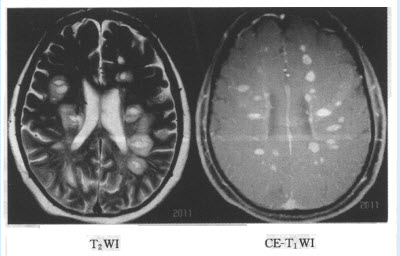

(单选题)最可能的诊断是()

A:子宫肌瘤

B:卵巢囊腺癌

C:卵巢囊腺瘤

D:卵巢囊肿

E:畸胎瘤

F:巧克力囊肿

(多选题)该病鉴别诊断()